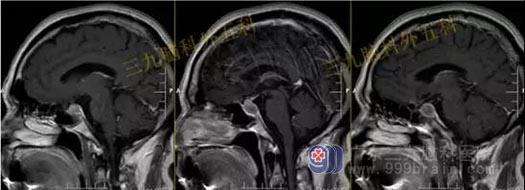

头部MR检查提示:

鞍区占位,现:鞍内垂体前叶示一类圆形异常信号,呈各序列内低外高信号影,增强后未见强化,范围约为1.2cm×1.2cm×0.7cm,视交叉略受压,大致同前。

手术过程:内镜下经鼻蝶鞍区rathke囊肿切除术,术中打开鞍底,保护正常垂体,在下方最薄弱上台垂体,可见胶冻样囊液,给予全切,术中垂体、鞍膈保护良好,无脑脊液漏形成。

术后复查头部MR检查提示:经鼻蝶鞍区占位性病变切除术后改变,原病灶已切除。